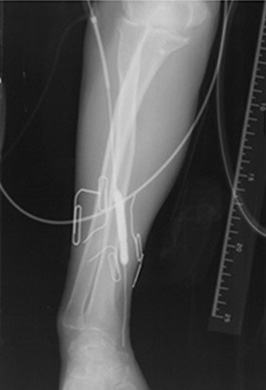

シャント狭窄の場合の治療法は、以下の通りです。

皮ふを切らずに針穴からたたんだ風船を入れ、狭いところを拡げる治療で、拡げ終わった後には風船は抜き去ります。入院の必要はありません。

PTA後血管造影図1 PTA(風船で狭いところを拡げる図)

図2 PTAに使用する道具